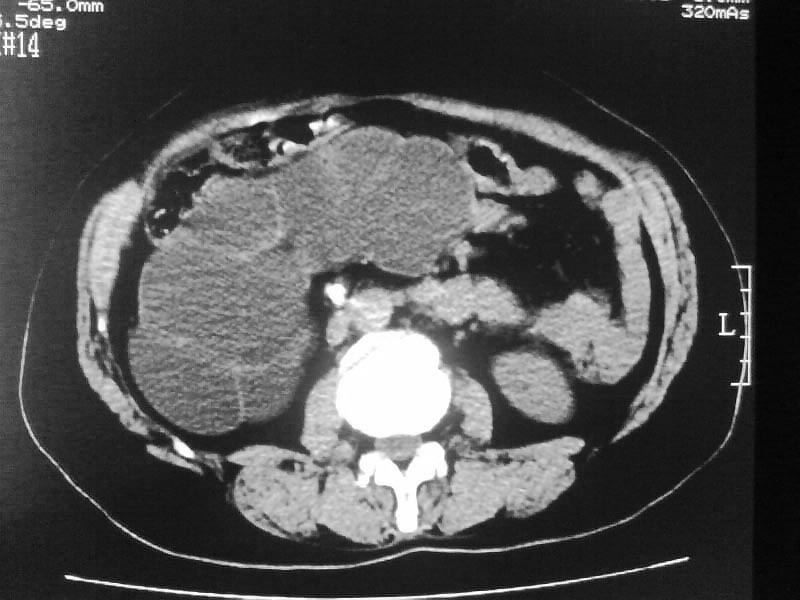

标题: CT20044:女,45岁,腰痛2年,双肾结石,右输尿管结石,右肾重度积 [打印本页]

标题: CT20044:女,45岁,腰痛2年,双肾结石,右输尿管结石,右肾重度积

支持双肾结石、右输尿管上端结石,右肾重度积水

右肾梗阻性积水。

支持 右肾结石、右输尿管上端结石,右肾重度积水。

双肾结石、双输尿管结石并右肾积水。